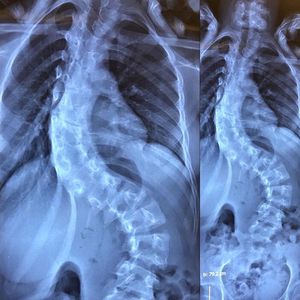

This abnormal lateral curvature of the spine is a condition called Scoliosis. In scoliosis, the patient’s spine is curved from side to side or front to back, and may also be rotated. On an x-ray, the spine of an individual with a typical scoliosis may look more like an "S" or a "C" than a straight line. It is quite common in young individuals and is often idiopathic and asymptomatic. In some cases, however, it is the result of underlying structural or neurological abnormalities. The majority of cases are idiopathic, meaning there’s no apparent underlying cause. Other reasons for scoliosis are broad, including congenital (from birth), neuromuscular scoliosis seen in spina bifida and patients with cerebral palsy, degenerative scoliosis due to a trauma, major previous back surgery, or osteoporosis. Surgical correction is done in curvatures of over 45 degrees and typically involves the use of modern instrumentation systems in which hooks and screws are applied to the spine to anchor long rods, ensuring the correction of the curvature and its stability over time.